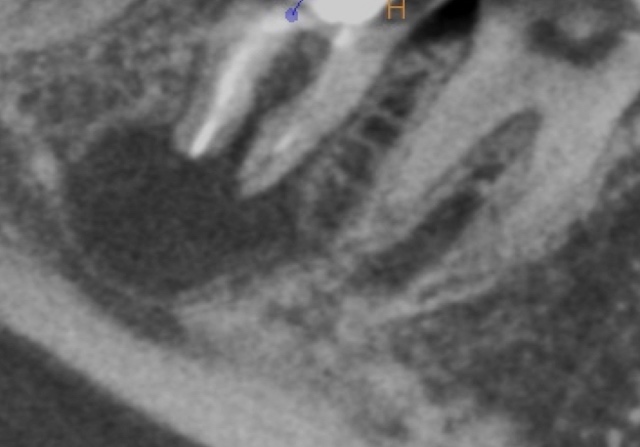

かぶせ物が不適であること(青矢印部)、近心根に根尖病巣があること(青枠部)、根充剤がかなり太いため(赤矢印部)歯質が薄くなっていることなど問題点がいくつかありましたが、他院で治療をしたばかりであり、また上記の条件から再治療には抜歯のリスクが非常に高いことから初診時は患者さんと相談し経過観察することになりました。